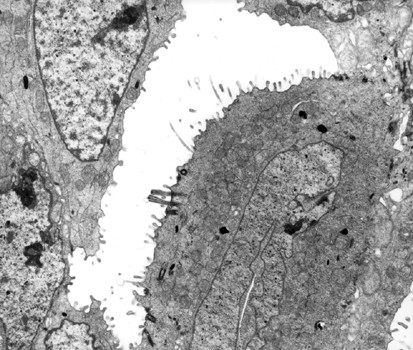

Figure 13 | Modern Pathology